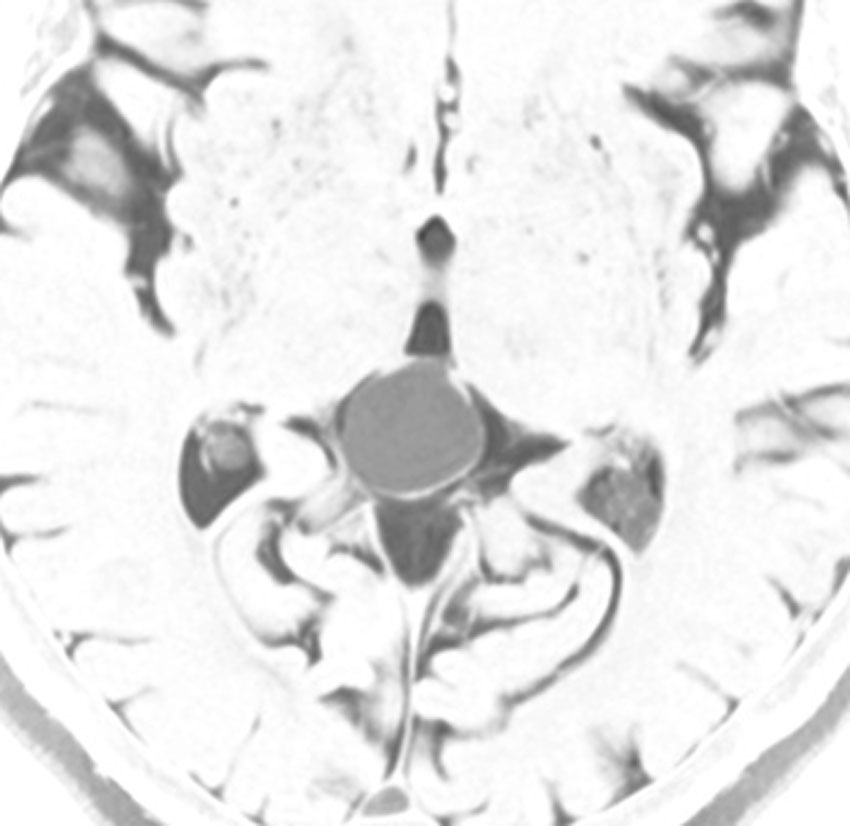

これも成人女性に偶然見つかった松果のう胞です。少し大きめですが,何も治療する必要はありません。中脳水道という所が狭くなっていますが,はっきり閉塞するまでは治療はしません。左がT1強調画像で黒っぽく見えます。右はT2強調画像で白く映っています。